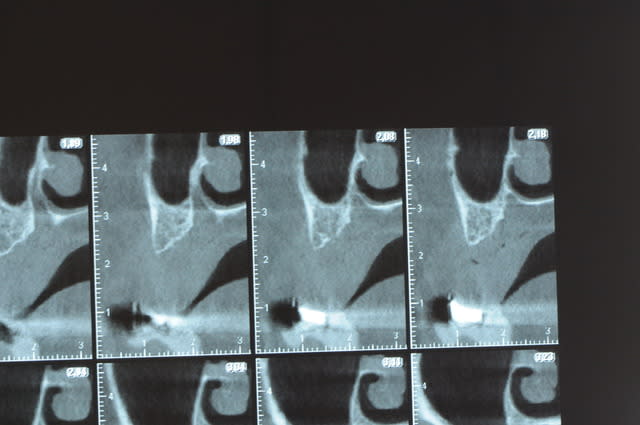

Une petite étude de ton cas D57

Les zones exploitables radiologiquement parlant:

Coupes implant

2,3 40100

4,96 35130 avec sinus lift mais difficile

5,25 35150

6,02 35130

6,78 35115 après réduction de hauteur de crête

7,26 35115 après réduction de hauteur de crête

8,51 35150

10,43 40115 ou 50115

11,10 40115

Ce qui nous fait 9 implants possible évidement avec un comblement de sinus on augmenterait encore les zones implantable mais ce n’est pas le but recherché, avec 8 (4+4) il doit être possible de faire une belle barre support de complet